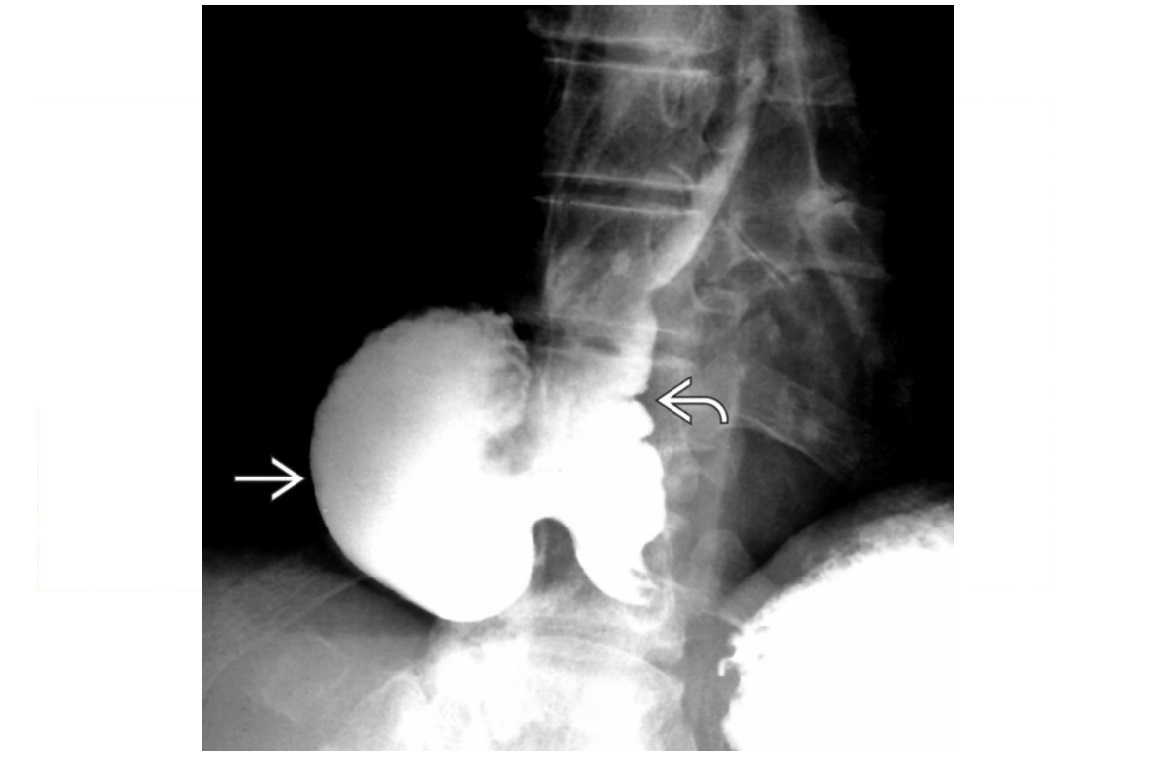

Epiphrenic diverticulum

Large saccular outpouching just above the diaphragm, right side

Can be mistaken for paraesophageal hernia - usually in on the left

associated with dysmotility disorders